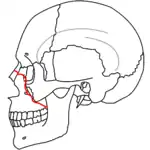

At the beginning of the 20th century, René Le Fort mapped typical locations for facial fractures; these are now known as Le Fort I, II, and III fractures (right).[7] Le Fort I fractures, also called Guérin or horizontal maxillary fractures,[14] involve the maxilla, separating it from the palate.[15] Le Fort II fractures, also called pyramidal fractures of the maxilla,[16] cross the nasal bones and the orbital rim.[15] Le Fort III fractures, also called craniofacial disjunction and transverse facial fractures,[17] cross the front of the maxilla and involve the lacrimal bone, the lamina papyracea, and the orbital floor, and often involve the ethmoid bone,[15] are the most serious.[18] Le Fort fractures, which account for 10–20% of facial fractures, are often associated with other serious injuries.[15] Le Fort made his classifications based on work with cadaver skulls, and the classification system has been criticized as imprecise and simplistic since most midface fractures involve a combination of Le Fort fractures.[15] Although most facial fractures do not follow the patterns described by Le Fort precisely, the system is still used to categorize injuries.[5]